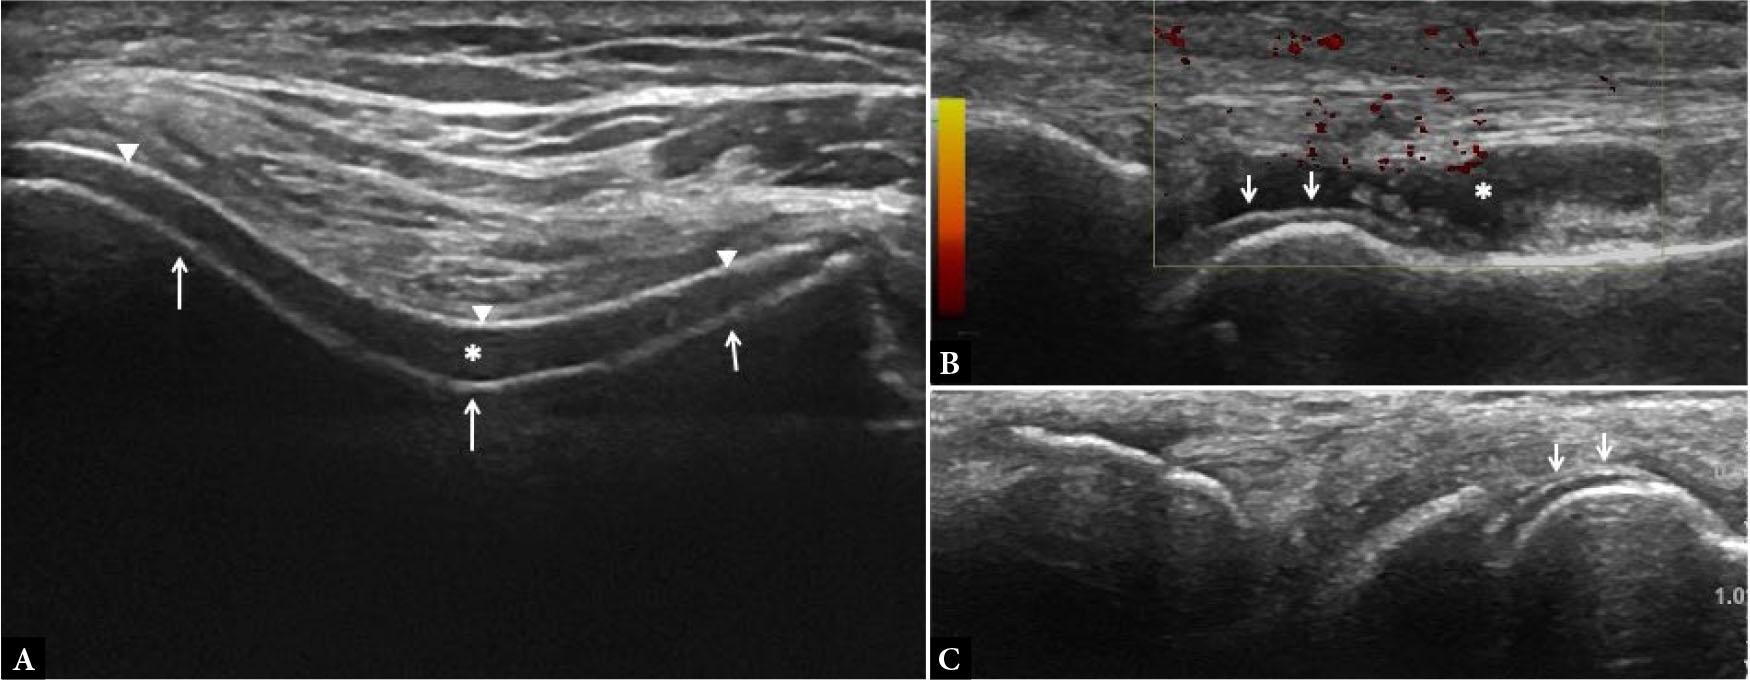

Fig. 11.

Tenosynovitis. Long- (A) and short-axis (B,C) US images of the 2nd extensor compartment tendons at wrist joint show circumferential hypoechoicteno-synovial proliferation (arrows in A and B) with significant power Doppler signal (arrow in C) suggestive of active tenosynovitis, in a known case of RA